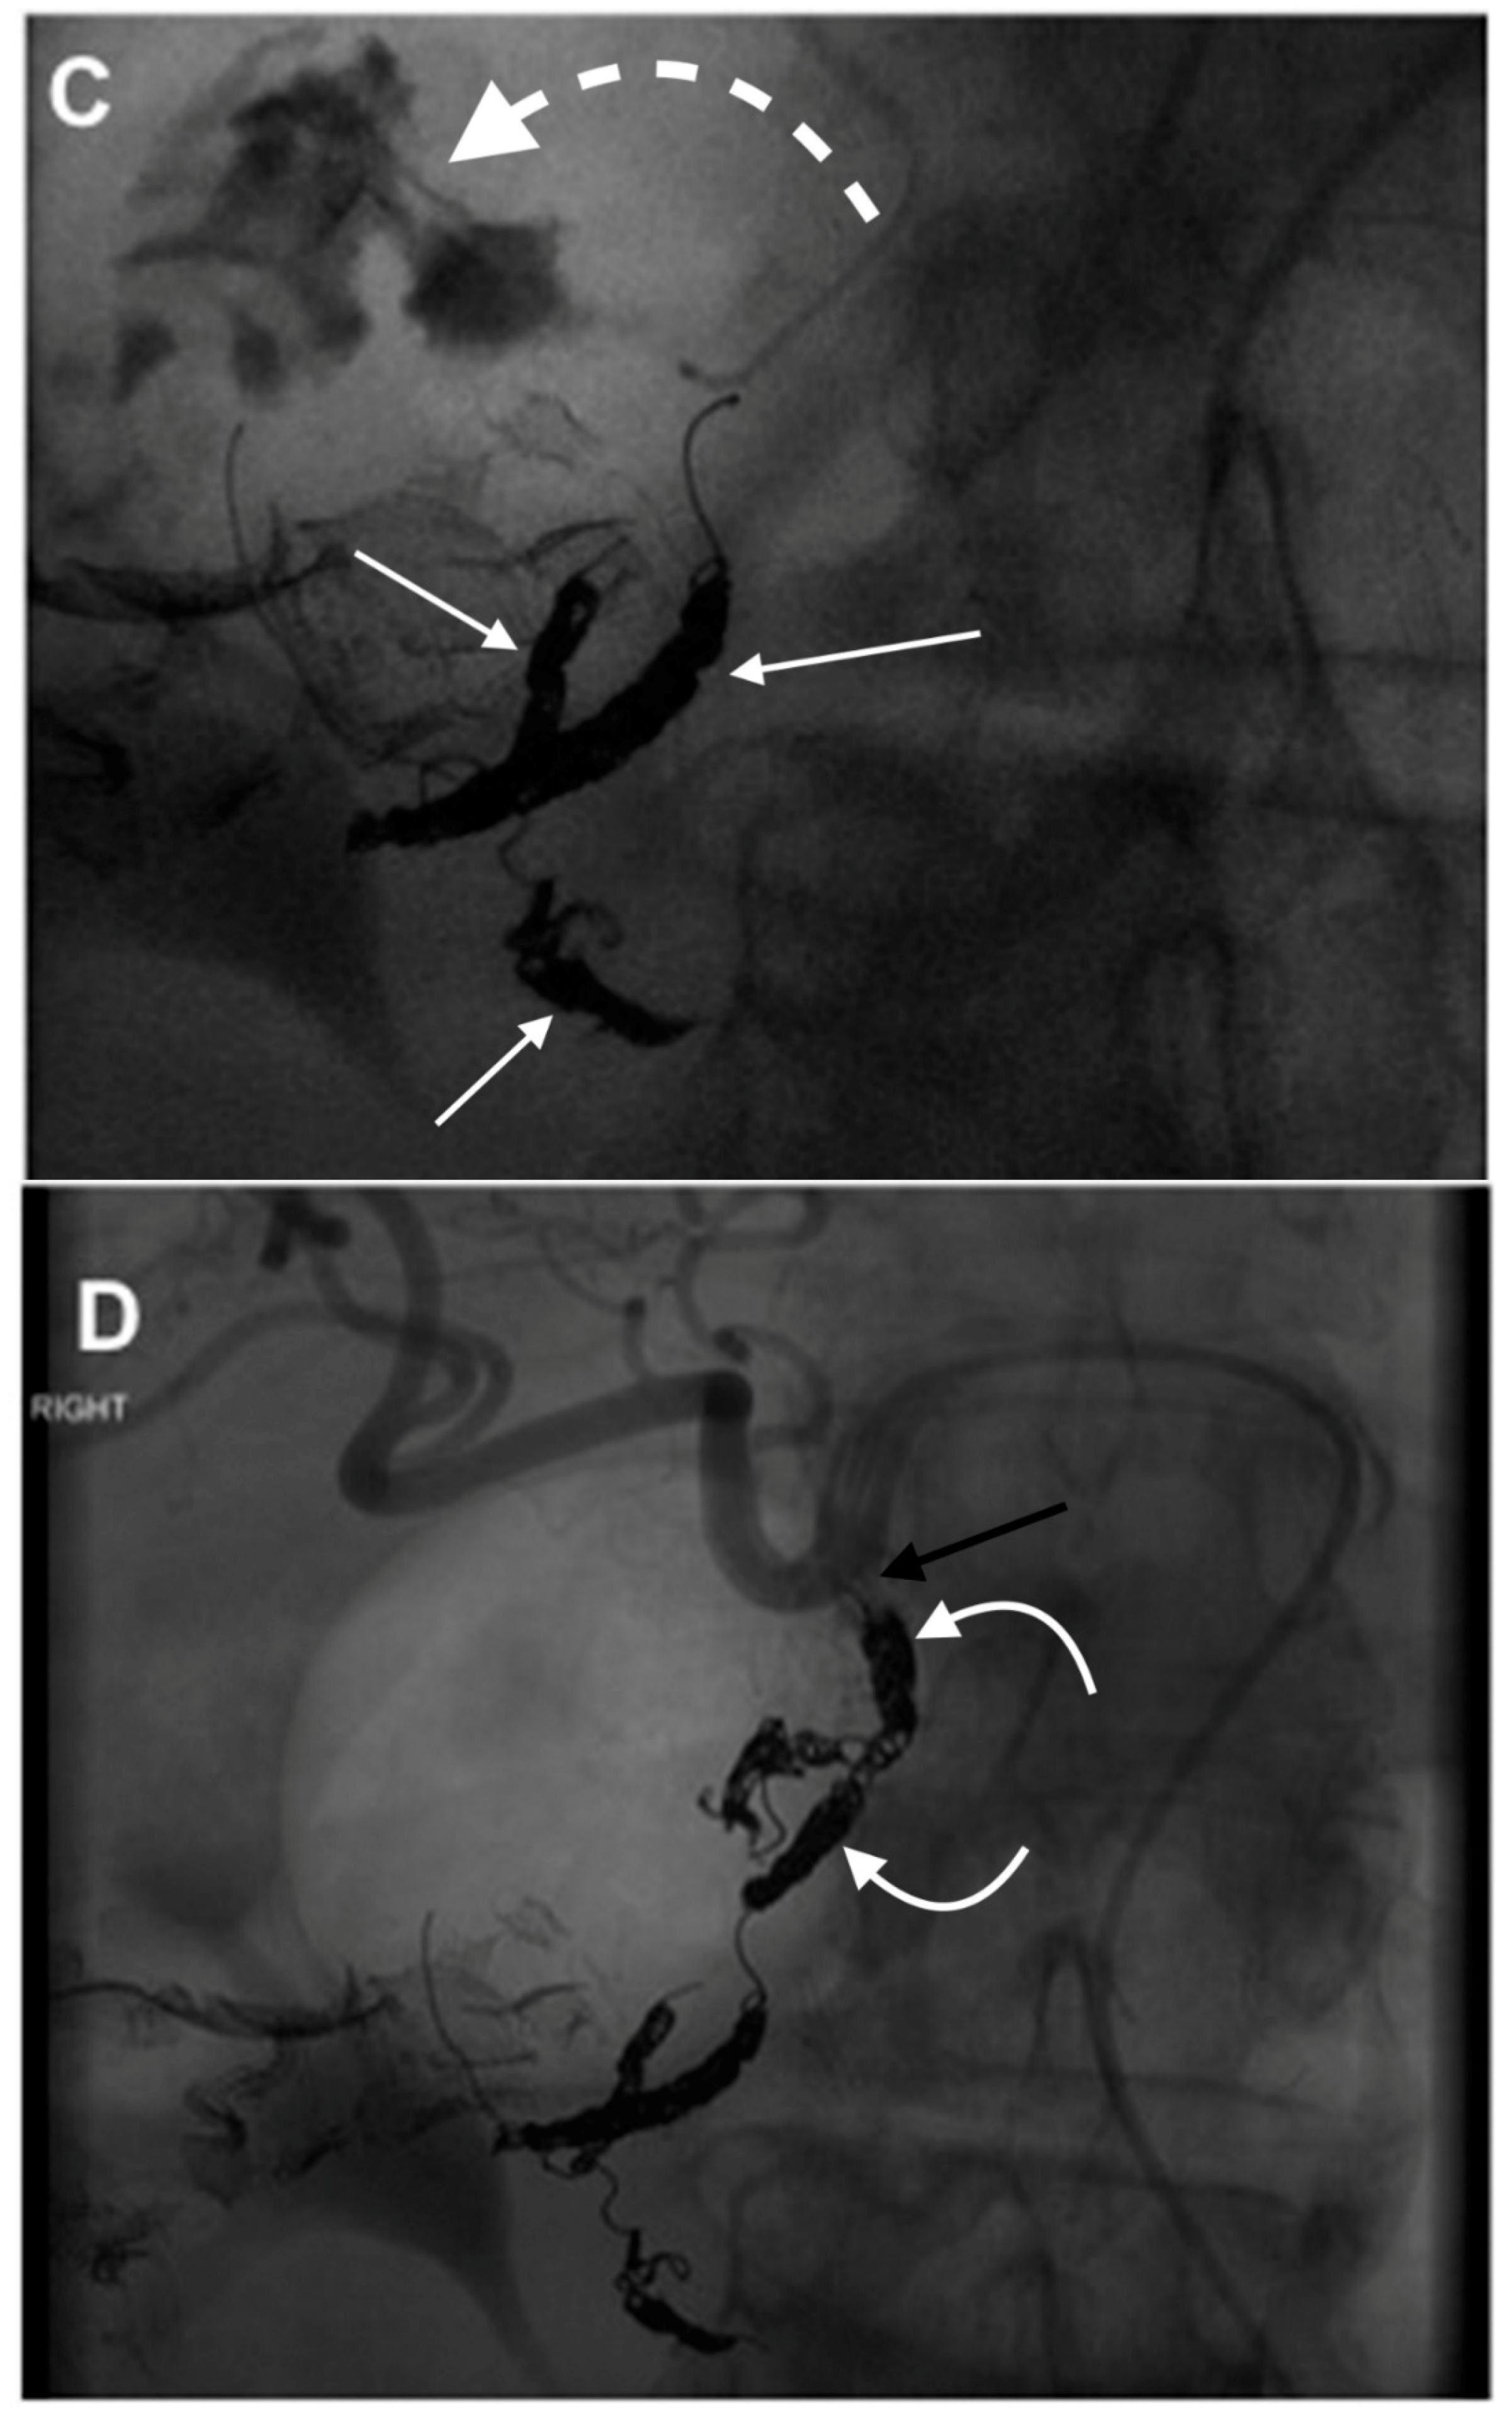

3. GDA Embolization in Gastrointestinal Bleeding

4. GDA Pseudoaneurysm Embolization

5. Pre-Y-90 GDA Embolization